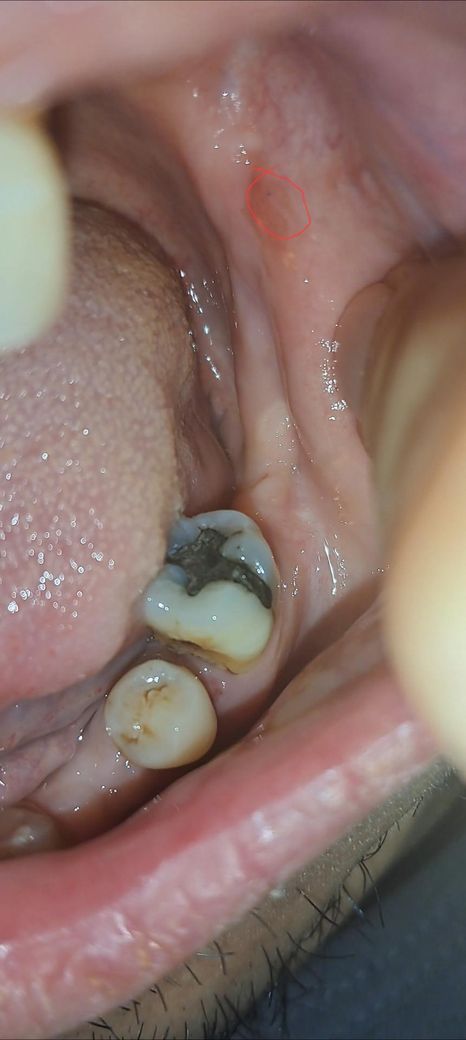

볼안쪽에 1미리미만 검은점이 생겼어요

오늘 보니 볼안쪽에 1미리미만 검은점이 생겼어요

지워지나 싶어 점막을 뜯어 봤지만 그대로 입니다

구강암증상이 아닌지 걱정됩니다

사진상으로 보이는 병변은 볼 점막에 국한된 1mm 미만의 매우 작은 검은 점으로, 표면이 비교적 매끈하고 궤양이나 출혈, 주변의 딱딱한 침윤 소견은 없어 보입니다. 이런 양상은 구강암보다는 점막 멜라닌 색소 침착, 미세한 점막하 출혈(아주 작은 멍), 치아나 보철물에 의한 반복적 자극 후 생긴 색소 변화, 드물게는 치과 치료 후 남은 금속 색소 침착(아말감 타투) 등 양성 원인일 가능성이 훨씬 높습니다. 구강암은 보통 크기가 점점 커지거나, 경계가 불규칙하고, 잘 낫지 않는 궤양, 쉽게 피가 남, 만지면 단단함, 통증이나 감각 이상이 동반되는 경우가 많습니다. 현재 설명과 사진만으로는 그 전형적인 모습과는 거리가 있어 보입니다. 다만 2주 이상 크기나 색이 변하지 않거나 점점 커지거나, 주변이 단단해지거나, 통증·출혈이 생기면 치과 구강외과나 이비인후과에서 직접 육안 및 촉진으로 확인받는 것이 안전합니다. 지금 단계에서는 경과 관찰이 합리적인 판단으로 보입니다.